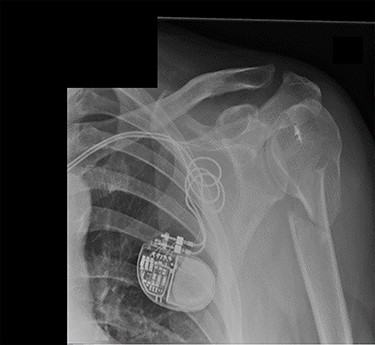

Examination and imaging of the patient revealed that during the fall, he had sustained a left surgical neck of humerus fracture (Fig. 1). Significant skin puckering was noted on the anterior aspect of the left shoulder over the fracture site, otherwise the arm was neurovascularly intact (Fig. 2). He was immediately reviewed by the orthopaedic team who offered surgical fixation of the fracture on the following morning, which was dependent on an appropriate anaesthetic assessment. The patient was in agreement and consented to proceed.

Antero-posterior view X-ray taken on day of admission, showing a left surgical neck of humerus fracture with anterior displacement of the proximal humeral shaft.